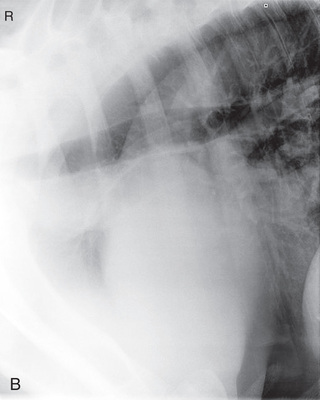

| Stifle | Caudocranial CdCr (Standard) | Caudoproximal-craniodistal standing (CdPr-CrDi) | Weight-bearing with limbs evenly on ground and vertical cassette against cranial aspect of patella at right angle to body wall, placed as far proximal and pushed as far medially as abdomen permits. | Caudal to the joint and directed downward to obtain a “tunnel” view of the distal femur. |

| Lateral (Standard) | Lateromedial | Weight-bearing with limbs evenly on ground and cassette against medial aspect of joint. | Laterally, parallel to the ground and centered distal and caudal to the patella. | |